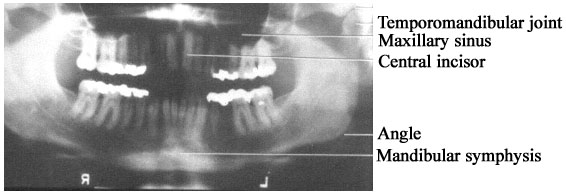

2.3  Panorex

Panorex คือ การถ่าย pantomography ใช้ดู mandible และความโค้งและความผิดปกติของฟันดังรูป sk 12

รูป sk 12 Panaromic tomogram